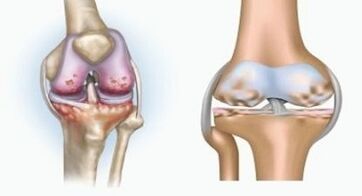

The two pathologies affect the joints, but differ in the nature of changes.

Arthritis is an inflammation of connective tissue - a synovial membrane which contains many vessels and provides a lymphatic flow.The inflammatory process leads to a violation of the nutrition of joint tissues, following which the production of joint lubrication - the synovial fluid is limited.

Osteorate

Osteoarthritis is a dystrophic degenerative process associated with the destruction of the cartilage tissue of the joint.The cartilage is gradually destroyed, dry, the distance between the bones of the joint decreases, which is the cause of the pain.In serious forms, destruction affects bones.They become more porous, lose their density, become fragile.

For example, what is the difference between arthritis and osteoarthritis of the knee joint?With arthritis, the synovial shell of joint tissues occurs.This causes an increase in the temperature of the joint.

The joint swells, a persistent pain syndrome develops, intensifying during movement.With osteoarthritis, pain only occurs after physical activity, you can hear a characteristic crunch or clicks in the joint, gradually the joint is distorted and loses mobility.

The difference between arthritis and osteoarthritis of the fingers and hands of the hands is that the first disease is cured and that the second is not.With arthritis, synovial shell and the joint capsule are affected.

The defeat of cartilage and bone tissue only occurs in late stages in a neglected state.With osteoarthritis, the cartilage fabric is first affected, then the bone, the inflammation of the synovial membrane is of secondary origin, that is to say that it develops on their history.